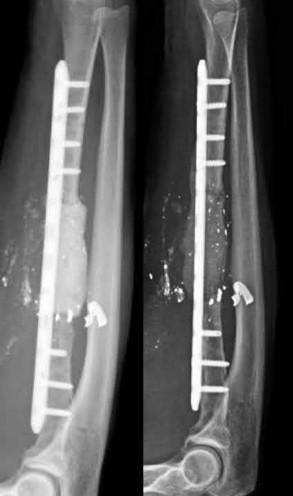

Question 29:

Correct Answer: Decreased local arteriovenous pressure gradient due to increased interstitial fluid pressure

Acute compartment syndrome occurs when elevated intracompartmental pressure leads to decreased local blood flow. The primary pathophysiologic event is an increase in tissue fluid pressure that eventually surpasses venous pressure, causing venous outflow obstruction. This leads to a collapse of the local arteriovenous pressure gradient. Without a sufficient AV gradient, capillary perfusion ceases, leading to microvascular compromise and subsequent tissue ischemia. Arterial pulses often remain palpable because the pressure required to occlude a major artery is much higher than that required to arrest capillary flow.